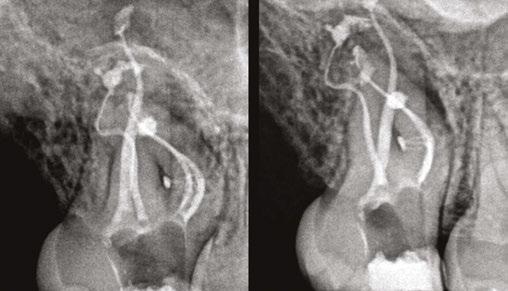

Figure 3: Second maxillary molar with external root resorption (ERR) with incidentally captured ERR on the lower mandibular first molar as well. When there is one tooth with resorption, be suspicious of other teeth with resorption, especially on younger patients Figure 6: No PARL on PA film. Clear PARL on scan taken with medicament Figures 4 and 5: 4. Mandibular molar with a J-shaped lesion due to endo — not a vertical root fracture. Path of least resistance happens to be through a distal perio pocket, but this is an endo-perio lesion and not a VRF. Incidentally, a mucous retention cyst was captured in the sinus. 5. Healing after bridge removal and retreatment

a realistic prognosis. Unfortunately, not all teeth can be saved. Some are not candidates for retreatment (Figure 11). Without a CBCT scan, it would be easy to attempt these retreatments only to discover the true problem mid-treatment, or worse — to think I had caused one (Figures 10 and 11). This added information not only helps the practitioner, but also provides patients a higher level of confidence and trust in you.

With retreatments, maybe the root canal looks completely fine on a PA or panoramic x-ray, but the patient says that it just doesn’t feel right. A cone beam can often reveal the cause of the patient’s discomfort. This could be that the tooth was perforated, cracked or has an unfilled canal, and the patient is totally justified in feeling like something’s wrong. Or sometimes the scan will show that there is another issue on an adjacent tooth or in the patient’s sinuses (causing their discomfort). When patients sense a problem but are told that there is not one (usually based on 2D radiographs), that’s not a great feeling. Being able to show the patient the CBCT scan and say, “You were right, and here’s the issue,” improves the patient experience.